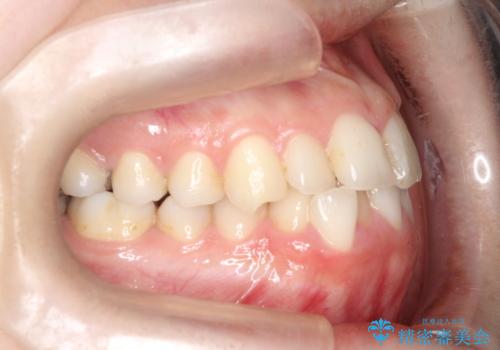

【ワイヤー矯正】前歯の凸凹を非抜歯で治療

- 前歯の凸凹を主訴に来院されました。

側方拡大にてスペースを作ることにより綺麗に前歯を並べることができました。

前歯の凸凹がある場合は治療計画を立てる上でスペースをどのように作るかが重要になります。

今回の場合は主に側方拡大でスペースの確保を行いました。